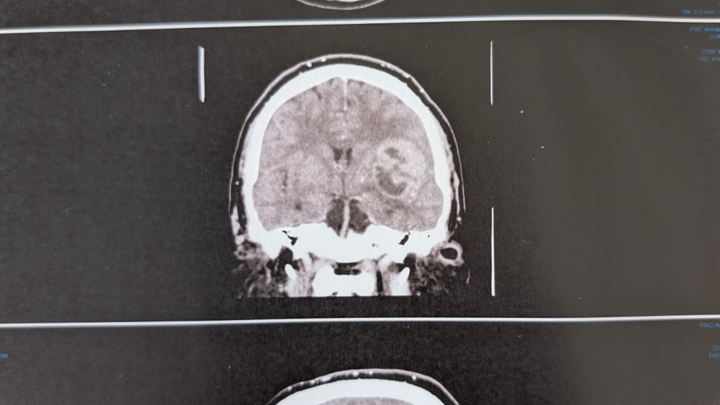

Last week at work Blair was located on site at work in a state on non-coherence and an ambulance was called by his fellow workers. Since that time he has been in hospital undergoing a barrage of tests which have revealed a brain tumor.

Blair did not expect this and was most grateful for the thought. He gave permission for the photos to be used.